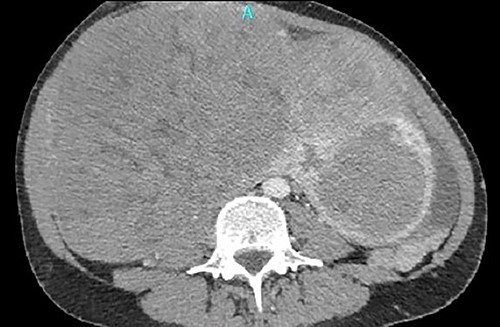

A single 46-year-old woman had a known history of huge uterine fibroids growing for the last 12 years. In her current presentation, the uterine with the fibroids was extending from the xiphoid to pubis, resulting in a recent common iliac vein thrombosis. The patient underwent a magnetic resonance imaging study of the abdomen, which showed enlarged uterine fibroids; the largest (21 cm in diameter) projected to the right lateral abdomen, compressing the gallbladder and the inferior vena cava (IVC).

One month later, after vascular consultation, a chest and pelvis computed tomography angiography was performed and a huge mass originating from the uterine wall was revealed (26 cm in diameter) (Fig. 1). The mass compressed the surrounding organs, especially IVC (Fig. 2). Furthermore, thrombosis of left femoral and external and common iliac veins, as well as infrarenal IVC patency (without clarification of IVC thrombosis), was detected. The common, internal and external right iliac veins were patent, and no PE was detected.